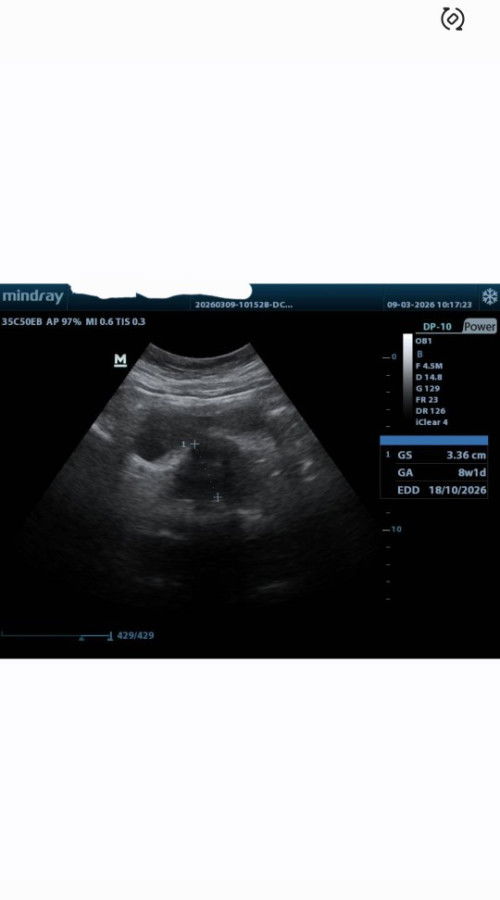

8weeks periksa di klinik oleh dokter umum

bun,disini adakah yg mengerti?,hari ini karena udab 8w ga sabar periksa. pas dateng ternyata yg periksa dokter umum dan usg. tapi katanya masih terlalu dini dan djj nya gabisa terdengar. tapi beliau bilang ada kantungnya.. tapi beliau sendiri ngomongnya kurang yakin huhu. kalau dari gambar apakah ada kantung dan calon janin nya bun?#mohonbantujawabbunda #Sharingdong_Bund